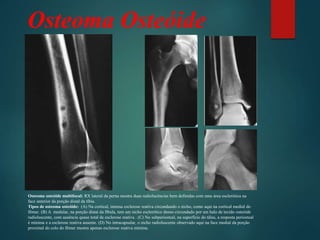

Osteoma osteóide multifocal: RX lateral da perna mostra duas radiolucências bem definidas com uma área esclerótica na

face anterior da porção distal da tíbia.

Tipos de osteoma osteóide: (A) Na cortical, intensa esclerose reativa circundando o nicho, como aqui na cortical medial do

fêmur. (B) A medular, na porção distai da fíbula, tem um nicho esclerótico denso circundado por um halo de tecido osteóide

radioluscente, com ausência quase total de esclerose reativa . (C) No subperiosteal, na superfície do tálus, a resposta periosteal

é mínima e a esclerose reativa ausente. (D) No intracapsular, o nicho radioluscente observado aqui na face medial da porção

proximal do colo do fêmur mostra apenas esclerose reativa mínima.